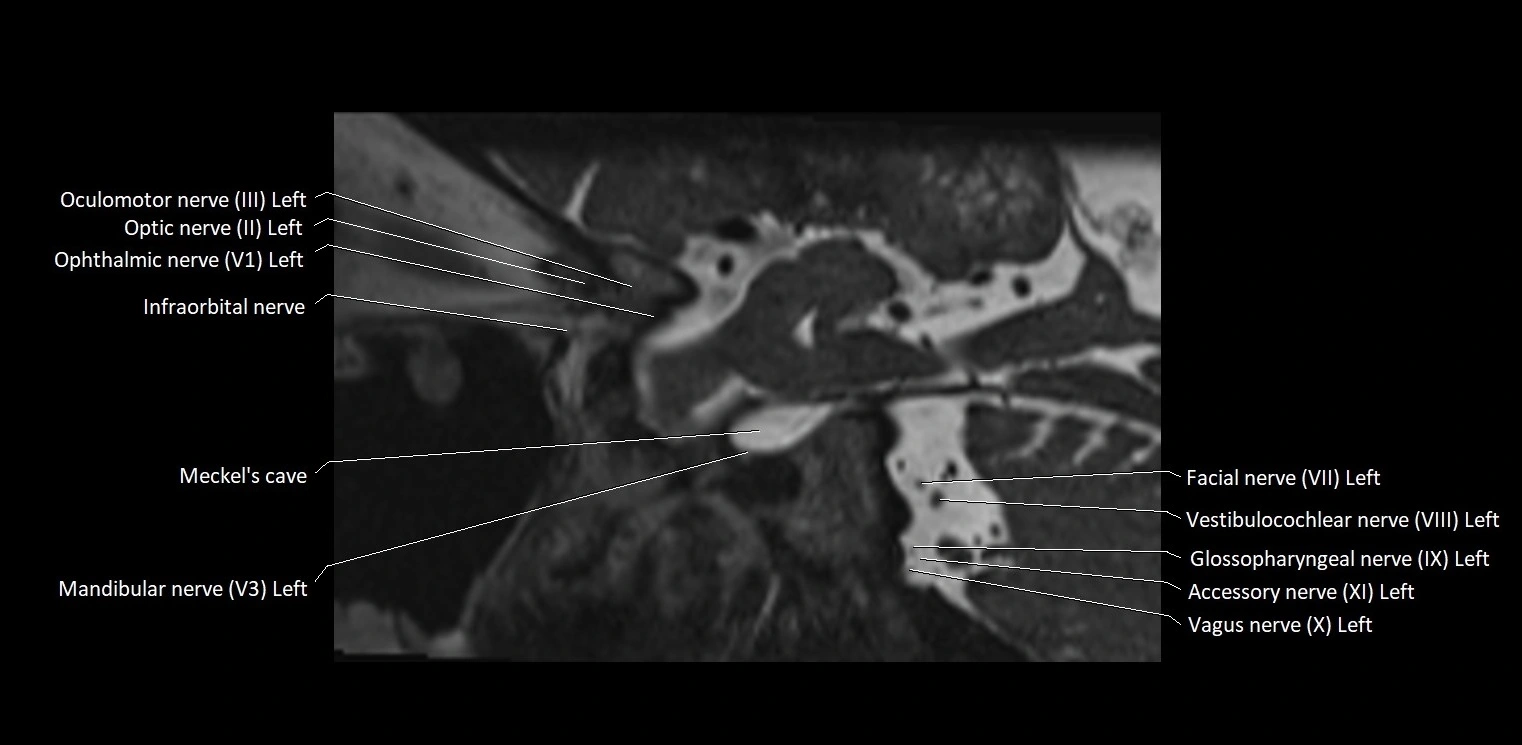

MRI Appearance

• The abducens nerve is a small, thin, linear structure

• Best visualized on high-resolution T2-weighted 3D MRI sequences (e.g., FIESTA or CISS)

• Seen as a hypointense (dark) line running from the brainstem at the pontomedullary junction, traversing the prepontine cistern, and entering Dorello’s canal under the petrosphenoidal ligament, then into the cavernous sinus, and finally the orbit

• May be challenging to visualize in standard MRI due to its small size

• Pathology may be inferred by absence, displacement, or enhancement of the nerve

MRI images

image